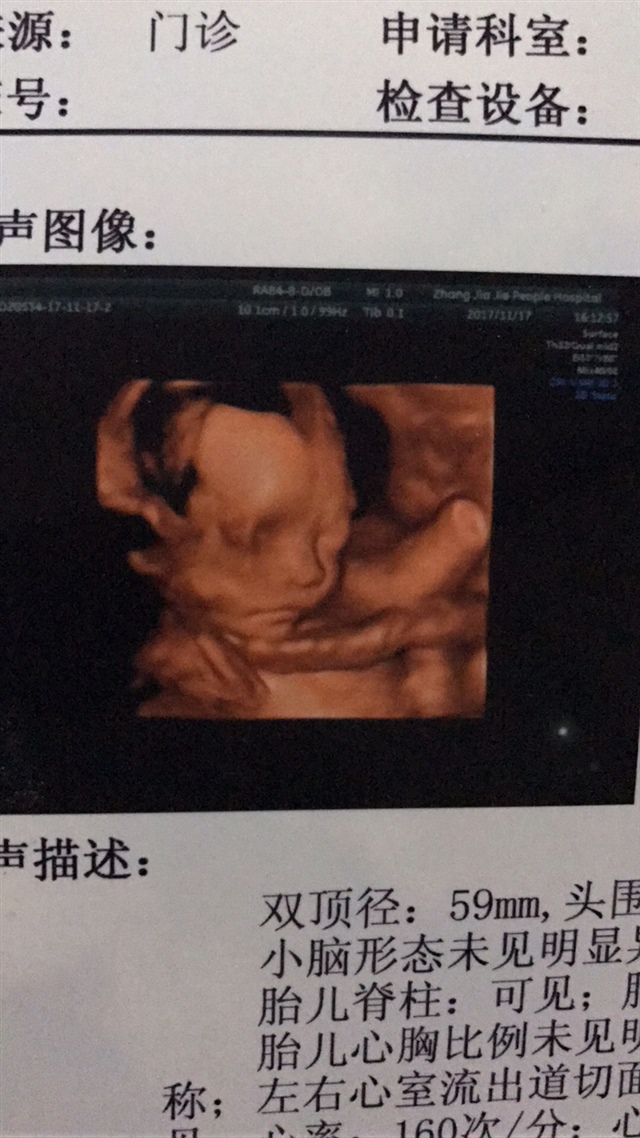

孕33周+0天

这是不是绕颈了啊,看着好像脐带在脖子上

认识你[帖主]:绕颈一周,现在没有了